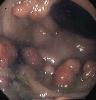

多數學者認為本徵的息肉屬於幼年型錯構瘤樣息肉。息肉有上皮細胞覆蓋,腺體增生而呈囊性擴張,分泌亢進,內含蛋白樣液或黏液。黏膜固有層血管充血,有慢性炎症水腫和明顯的嗜酸性細胞浸潤。息肉可分布在從食道到直腸的全消化道中的任何部位。

消化道鋇餐檢查,胃內有多發性結節狀或息肉樣充盈缺損,大小不等,大者可至3cm。胃黏膜襞影廣泛粗大,有時可被誤診為Menetrier病,即巨型肥厚性胃炎;小腸則顯示廣泛性息肉樣充盈缺損或腸黏膜粗厚,其中以十二指腸內最多。鋇劑灌腸或氣鋇雙重造影,結腸、直腸內息肉廣泛存在。有時息肉密集叢生,使結直腸腔內無正常黏膜可見。